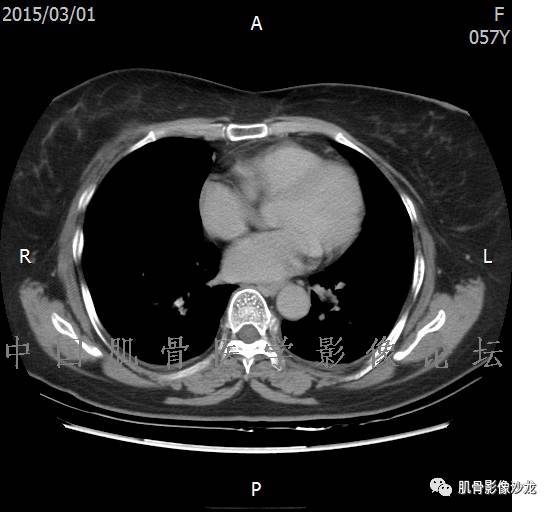

患者2月前无明显诱因下感右腿疼痛、麻木,疼痛呈持续性,发作时无法行走,休息后可缓解。当时无明显肿块,患者遂至当地医院就诊,查X片见右髂骨骨质破坏。6周前患者自觉右髋部渐大肿块,初肿块较小,后肿块逐渐增大,现肿块约12*10cm大小,有压痛。患者遂至我院就诊,查MRI:右髂骨异常信号,伴软组织肿块。ECT、肺CT未见转移。现患者为求进一步治疗,门诊拟“右髂骨肿块 ”收治入院。 患者发病来,神清,精神可,胃纳夜眠可,二便无殊,体重无明显变化。

1、软骨肉瘤可以有膨胀性骨质破坏(病例3,4),可以有溶骨性骨质破坏(病例2),局部皮质因为破坏变薄,中断 ;

2、软骨基质T2WI高信号,软骨小叶分叶状,也就会出现高老师提到的骨内膜扇贝形压迹。一般认为骨内膜扇贝形压迹超过骨皮质厚度的2/3是软骨肉瘤在长管状骨的特征性表现。如上图。3、软组织肿块或肿胀;

4、 钙化,环形,弓形,边缘模糊 ;

5、增强后进行性延迟,不均匀分割状强化, 会强化的纤维间隔,软骨小叶不会强化,关于老师们说到的钙化,软骨肉瘤不一定会有钙化 。